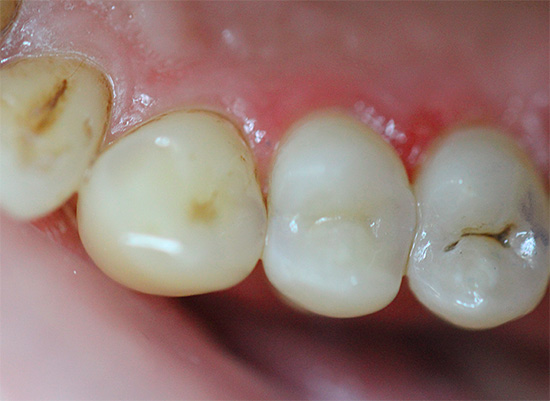

Un aspetto tipico dei denti con carie cronica è mostrato nella foto qui sotto:

Non ci sono lesioni estese dei denti e in alcuni punti le aree scure sono di dimensioni molto ridotte e spesso non attirano l'attenzione del paziente. Di solito il dolore è assente.

- La carie cronica nella fase spot quasi non si manifesta. Un dente può rispondere a cibi freddi o aria, ma questo non è percepito dal paziente come una patologia. L'area dello smalto demineralizzato appare come una macchia opaca biancastra sul dente.

- La carie superficiale cronica porta alla formazione di una cavità nello smalto dei denti, ma senza danni alla dentina. Tale cavità non ha bordi sporgenti, è ampia, ben aperta, lo smalto stesso di solito si scurisce a causa della pigmentazione, ma mantiene una durezza relativamente elevata.